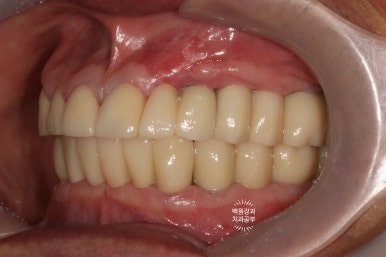

최종 보철물로 완전히 교체 후 구강내 사진입니다.

순차적으로 포스팅을 읽으신 분들은... 첫 모습을 이미 까먹으셨을텐데요...

처음 내원시 구강내 사진을 생각하신다면!!! 정말 놀라운 변화가 아닐 수 없죠...

제자리를 잃어버렸던 치아들이 모두 가지런하게 되었고,

치아 사이의 벌어진 틈은 지르코니아 보철물을 이용해서 모두 깔끔하게 채워드렸으며,

치아의 색상 또한 60대 남자 환자분의 피부색에 맞추어 어울리게 그리고 화사하게 바꿔드린 상태입니다.

금속색 하나 비춰보이는 것 없이 완벽하네요....

역시 저희 치과의 보철과 전문의 원장님의 장인정신은 혀를 내두를만 합니다.

최종보철물 완성 후 측면사진입니다.

임플란트가 저렇게 지그재그로 완벽하게 물리기 쉽지 않습니다.....

환자분의 인내심과 의료진의 노력으로 만들어낸 결과입니다.